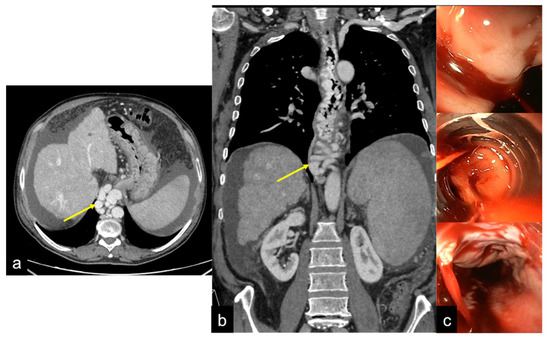

| Aorto-Enteric Fistula (Figure 31) | Bleeding in a patient with a history of surgery for aortic aneurysm. | A connection between the aorta and the intestinal lumen. Absence of adipose cleavage planes. |

| Haemobilia (Figure 32) | Melaena, haematemesis, biliary colic, jaundice, or massive bleeding in a patient with a history of blunt or iatrogenic abdominal trauma. | Presence of blood in the gallbladder and biliary tree. |